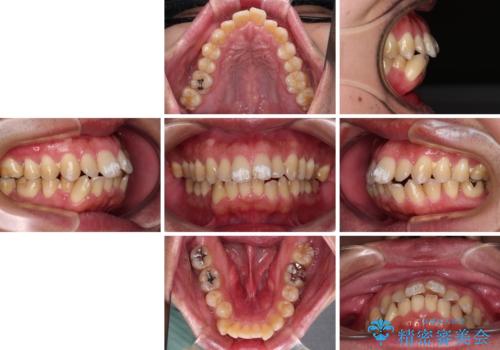

- 口が閉じられないとのことで来院された患者様です。

顎先に力を入れないと唇が閉じきれない口元であったので、上下左右の第一小臼歯4本を抜歯して、ワイヤー装置にて矯正治療を行うこととしました。